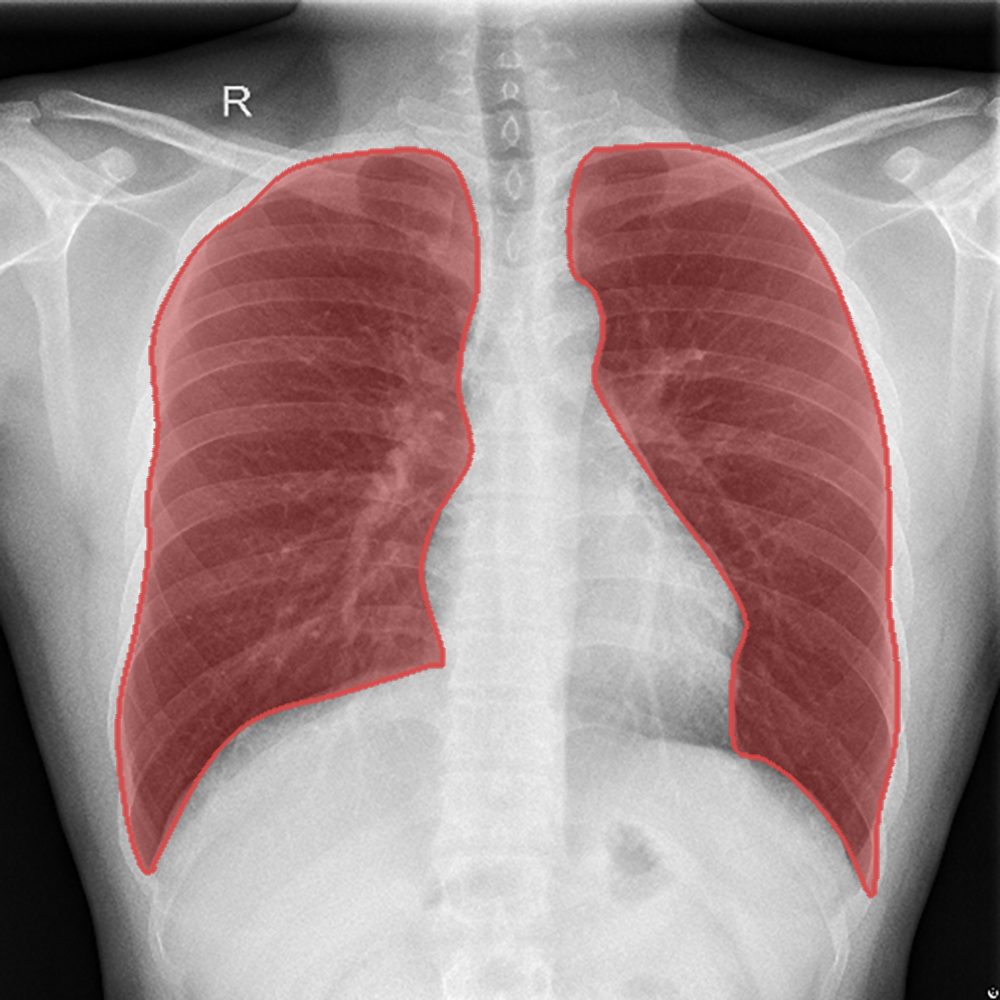

Introduction: We present a collection of lung segmentation models designed for accurate analysis of chest X-ray (CXR) images. These models have undergone rigorous training, validation, hyperparameter tuning, and testing on a diverse dataset consisting of CXRs from three publicly available sources: the Darwin, Montgomery, and Shenzhen datasets.

Dataset Description: The dataset includes CXRs from patients diagnosed with various respiratory diseases, including COVID-19, pneumonia, and tuberculosis. While these conditions differ in nature and disease patterns, we intentionally included them in the training data to improve the ability of the models to generalize across a range of pathologies. The dataset is summarized in Table 1 and publicly available at https://data.mendeley.com/datasets/8gf9vpkhgy/2.

Model Comparison: After a thorough evaluation, DeepLabV3+ emerged as our top choice. It exhibited exceptional performance with a DSCtest score of 0.963, while maintaining computational efficiency with a total of 7.4 million parameters and 2.2 billion MACs. This combination of high performance and computational efficiency solidified its position as the optimal model for our lung segmentation task.

Segmentation example - Shenzhen.png